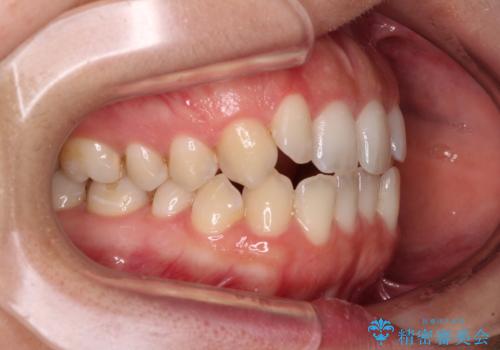

- 前歯の開咬を気にして来院された患者様です。

開咬の治療は、前歯を閉じるように動かすとともに、上下臼歯を圧下(骨内にめり込ませる)させることで進めて行きます。

インビザラインは臼歯の圧下を効果的に行えるため、インビザラインを用いて矯正治療を行うこととしました。